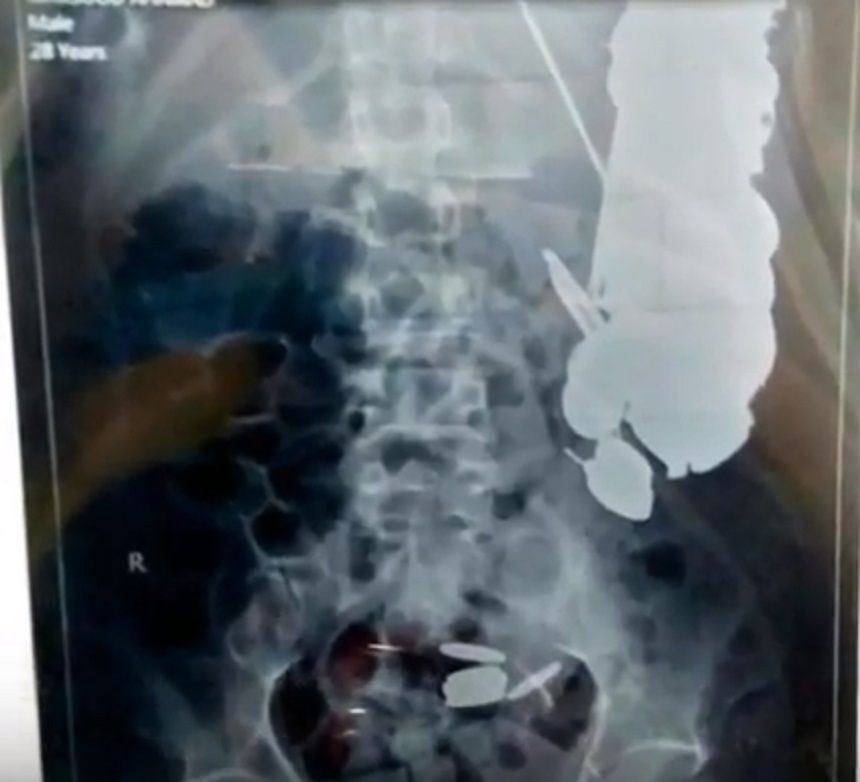

Medicii au gasit 263 de moneze si 1,5 kg de unghii, pietre si bucati de sticla.

Barbatul consumase un kilogram si jumatate de metal, iar in total, medicii au scos 7 kg de obiecte straina din corpul lui.